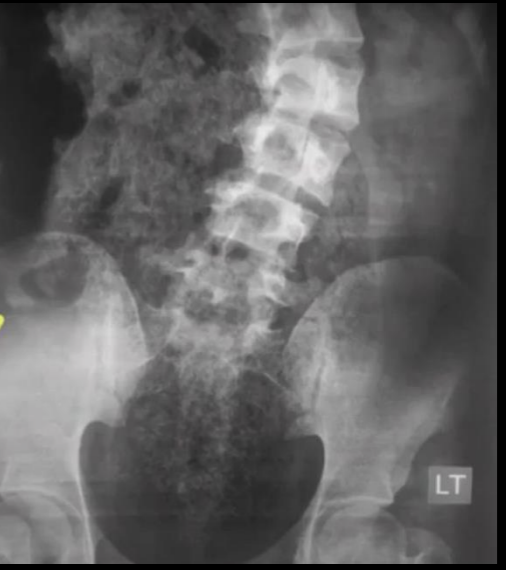

Apendicolito y Escoliosis antialgica

Borramiento del psoas e hiperdensida articular